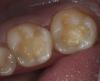

Art 7 Опубликовано 12 апреля, 2013 Поделиться Опубликовано 12 апреля, 2013 ситуация допрепарирование и оттиски были сделаны раздельно для каждой стороны3,6 и 3,74,6 и 4,7и готовая работа фиксировалась в одно посещение 4 Ссылка на комментарий

johniola Опубликовано 12 апреля, 2013 Поделиться Опубликовано 12 апреля, 2013 что?, что? вы про что?)это вкладки? 1 Ссылка на комментарий

Art 7 Опубликовано 12 апреля, 2013 Автор Поделиться Опубликовано 12 апреля, 2013 это вкладки?Да Ссылка на комментарий

Л Ю С Я Опубликовано 12 апреля, 2013 Поделиться Опубликовано 12 апреля, 2013 Скажите из чего вкладки? Правда что ль золото? Что- то не похоже, может я и не права, но напоминает амальгаму у меня аж дежавю какое- то случилось . Хотя врачебная работа гуд..! Ссылка на комментарий

Art 7 Опубликовано 12 апреля, 2013 Автор Поделиться Опубликовано 12 апреля, 2013 Скажите из чего вкладки? Правда что ль золото? Что- то не похоже, может я и не права, но напоминает амальгаму у меня аж дежавю какое- то случилось . Хотя врачебная работа гуд..!Вкладки из золота. Правда правда честно честно Ссылка на комментарий